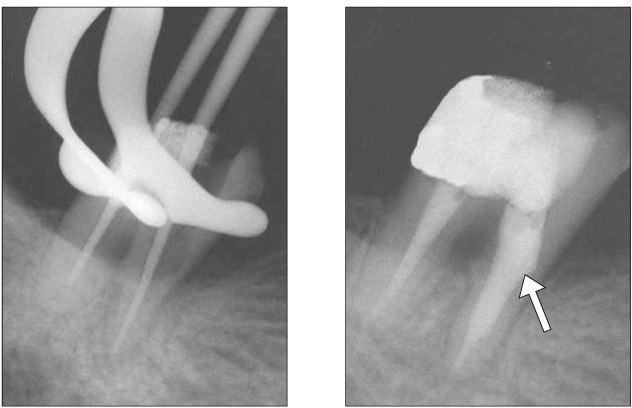

Figure 10

After intentional replantation (a), 3-month recall (b), 6-month recall (c) radiograph.

jkacd-31-161-g010.jpg

Figure 10 After intentional replantation (a), 3-month recall (b), 6-month recall (c) radiograph.